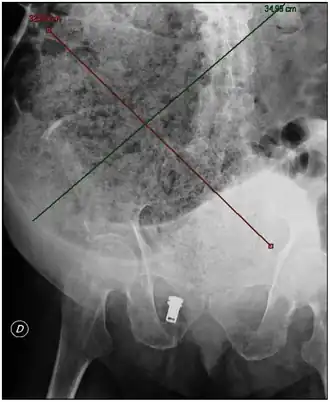

![]() Rayo X mostrando una amplia impactación fecal de más de 40 cm de longitud y 33 cm de anchura. | ||